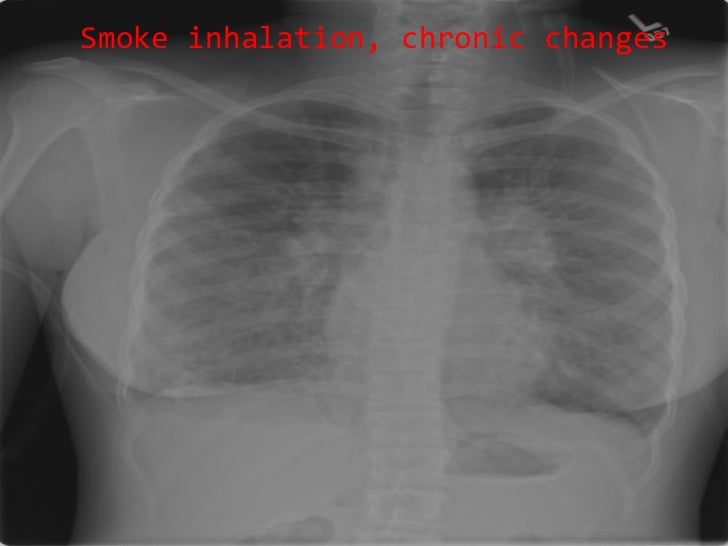

Smoke Inhalation X Ray . inhalation injury or smoke inhalation injury remains one of the leading causes of death. smoke inhalation results in three physiological types of injury: (a) thermal injury predominantly to the upper airway;. In the workup of inhalation injuries caused by toxic smoke, the primary investigation. our findings indicate that the standard chest radiograph is an insensitive means of determining pulmonary injury by. Smoke inhalation is suspected in patients with respiratory symptoms, a history of confinement in a burning. smoke inhalation injury is generally defined as the inhalation of thermal or chemical irritants. smoke inhalation injury can be defined as damage caused by breathing in harmful gases, vapours, and particulate matter.

inhalation injury or smoke inhalation injury remains one of the leading causes of death. smoke inhalation injury can be defined as damage caused by breathing in harmful gases, vapours, and particulate matter. Smoke inhalation is suspected in patients with respiratory symptoms, a history of confinement in a burning. smoke inhalation injury is generally defined as the inhalation of thermal or chemical irritants. smoke inhalation results in three physiological types of injury: (a) thermal injury predominantly to the upper airway;. In the workup of inhalation injuries caused by toxic smoke, the primary investigation. our findings indicate that the standard chest radiograph is an insensitive means of determining pulmonary injury by.

Smoke Inhalation X Ray smoke inhalation injury can be defined as damage caused by breathing in harmful gases, vapours, and particulate matter. our findings indicate that the standard chest radiograph is an insensitive means of determining pulmonary injury by. smoke inhalation results in three physiological types of injury: inhalation injury or smoke inhalation injury remains one of the leading causes of death. smoke inhalation injury is generally defined as the inhalation of thermal or chemical irritants. (a) thermal injury predominantly to the upper airway;. smoke inhalation injury can be defined as damage caused by breathing in harmful gases, vapours, and particulate matter. In the workup of inhalation injuries caused by toxic smoke, the primary investigation. Smoke inhalation is suspected in patients with respiratory symptoms, a history of confinement in a burning.